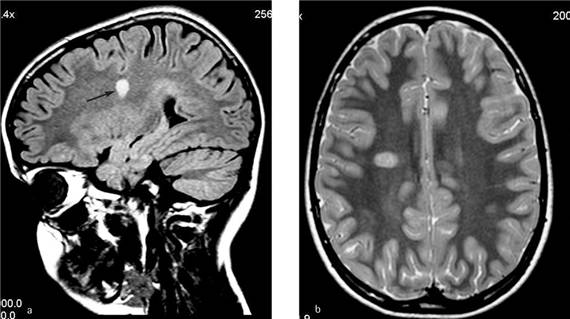

При рассеянном склерозе широкое применение нашли методы компьютерной томографии и магнитно-ядерной томографии (МРТ). При компьютерной томографии изображение получают только в аксиальной плоскости, при этом из-за лучевой нагрузки приходится ограничивать объем и частоту проводимых исследований. При MPT-исследовании имеется возможность проведения широкой вариабельности плоскостей изображения и одномоментное получение трехмерного изображения различных очагов поражения. Отсутствие лучевой нагрузки дает возможность многократного проведения исследования.

Информативность метода магнитно-резонансной томографии (МРТ) уже в начале развития рассеянного склероза достигает 80-90 %. При помощи этого метода удается выявить в веществе головного мозга даже самые маленькие участки патологически измененной ткани в объеме всего 2-3 мм3.

Метод контрастного усиления повышает диагностические возможности МРТ. Введение в вену непосредственно перед процедурой МРТ специальных контрастирующих препаратов гадолиния дает возможность определить как свежие бляшки, так и активность старых бляшек. В этих случаях в местах нахождения бляшек контрастное вещество просачивается через сосудистые стенки и дает резкое усиление сигнала. Повторные MPT-исследования позволяют проследить за динамикой патологического процесса.

С помощью МРТ установлено, что при рассеянном склерозе нарушается функция гематоэнцефалического барьера, в острой стадии заболевания вокруг патологического очага появляется зона отека. Отек постепенно уменьшается и даже исчезает по мере улучшения в течении болезни, особенно это заметно на фоне лечения кортикостероидами. Методом МРТ нередко определяется выраженное истончение зрительных нервов, уменьшение их поперечных размеров.

Исследование орбитального отдела зрительного нерва при рассеянном склерозе нередко показывает усиление сигнала МРТ. У части больных при этом обнаруживается усиление сигнала от клинически здорового второго глаза и расширение субарахноидального пространства его дистального отдела зрительного нерва. Почти у 70 % больных с оптическим невритом на почве рассеянного склероза обнаруживаются ретрохиазмальные поражения различной степени выраженности в наружных коленчатых телах, зонах зрительной лучистости Грациоле и около зрительных корковых центров затылочных долей мозга.

В ряде случаев клиническая ремиссия при рассеянном склерозе не означает ремиссию заболевания. Поэтому для того, чтобы оценить достоверную истинную активность болезни, следует не менее одного раза в год осуществлять МРТ-исследование головного мозга. Ежегодные исследования позволяют выявлять новые очаги заболевания и определять активность (или неактивность) старых очагов поражения. Поэтому весьма желательно проводить данные исследования на одних и тех же аппаратах, что дает возможность получить идентичные срезы для сравнения.

- выявление типичных изменений на МРТ головного мозга в виде не одиночного, а множественных очагов поражения мозговой ткани;